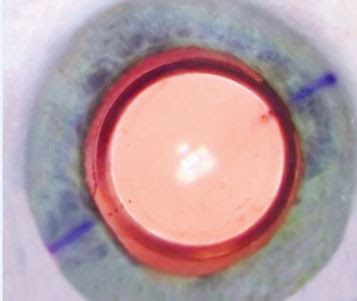

If you decide to have a TORIC IOL, on the day of surgery small ink markings are made on the surface of the cornea to mark the axis of your astigmatism.

The TORIC IOL also has markings (four small dots in a line), which will need to line up with the markings your surgeon has placed on your cornea (purple marks).